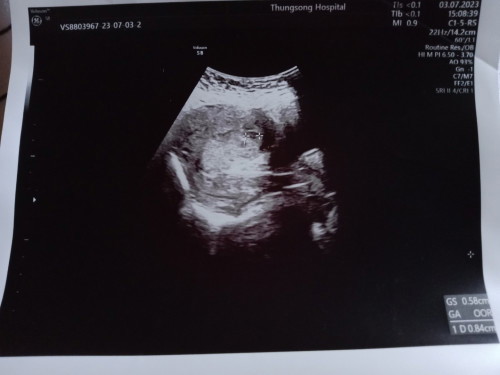

ซาวด์ไม่เจอเด็ก มีแม่ๆท่านไหนมีประสบการณ์แบบนี้ไหมคะ

มีแม่ๆท่านไหนไปอัลตร้าซาวด์แล้วไม่พบถุงการตั้งครรภ์บ้างมั้ยค่ะ บ้านนี้ไปซาวด์ตอน7วีค หมอบอกไม่พบถุงการตั้งครรภ์ อีก2วันนัดไปเจาะเลือดตรวจ ตอนนี้แม่เครียดมากเลยอยากรุ้ว่ามีคนเป็นเหมือนเรามั้ย ไปเปิดกูเกิ้ลดู ส่วนมากที่ไม่เจอถุงตั้งครรภ์เพราะอายุครรภ์น้อย